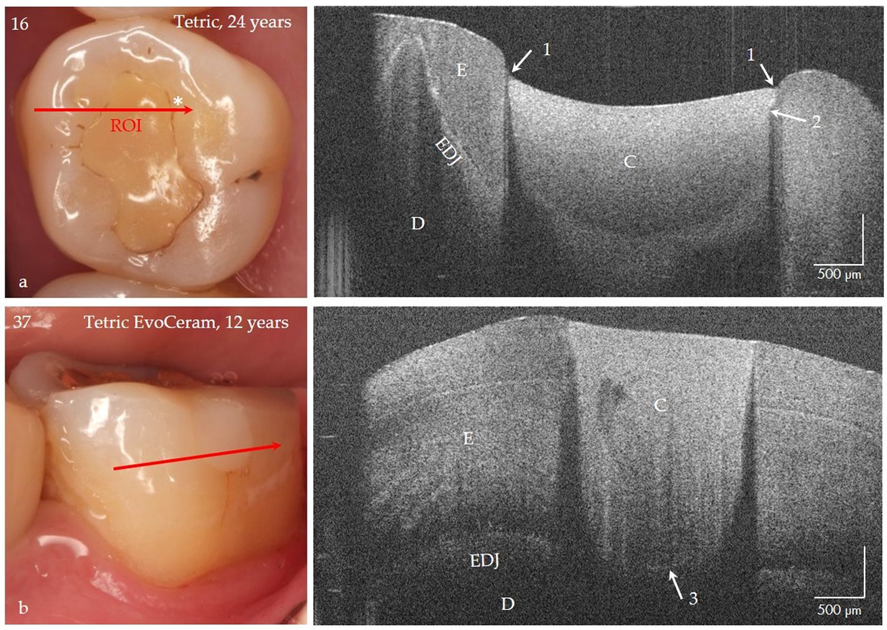

Figure 15.

Class I and V composite restorations (C) in teeth 16 and 37 after 24 and 12 years of clinical function, imaged with OCT from the occlusal (a) and vestibular view (b). (a) The surface of the composite restoration (Tetric, adhesive #) shows negative steps at the restoration margins (arrows 1). The marginal discoloration (*) can be explained by the short interfacial marginal gap and not by caries adjacent to the restoration margin (secondary caries) (arrow 2, bright line). Beyond that the bonding interface is still intact after 24 years (no bright signal lines) and the material is homogeneous. (b) At the floor of the 12-year-old restoration (Tetric EvoCeram, adhesive #) a short interfacial gap (3) is indicated, the progression of which can be monitored. Compared to tooth 16, the restoration margins are flat, and the material exhibits inhomogeneities. Enamel (E), dentin (D), the enamel-dentin junction (EDJ). The red arrows mark the section planes of the OCT cross-sectional images. The vertical scales are related to the refractive index n = 1.0 (see remark in Figure 4).